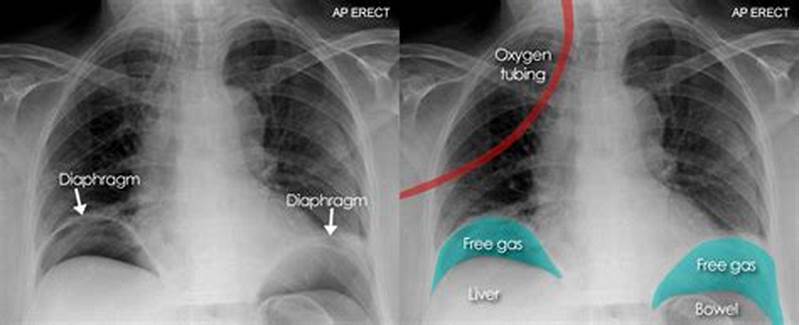

Abnormal Gas Pattern